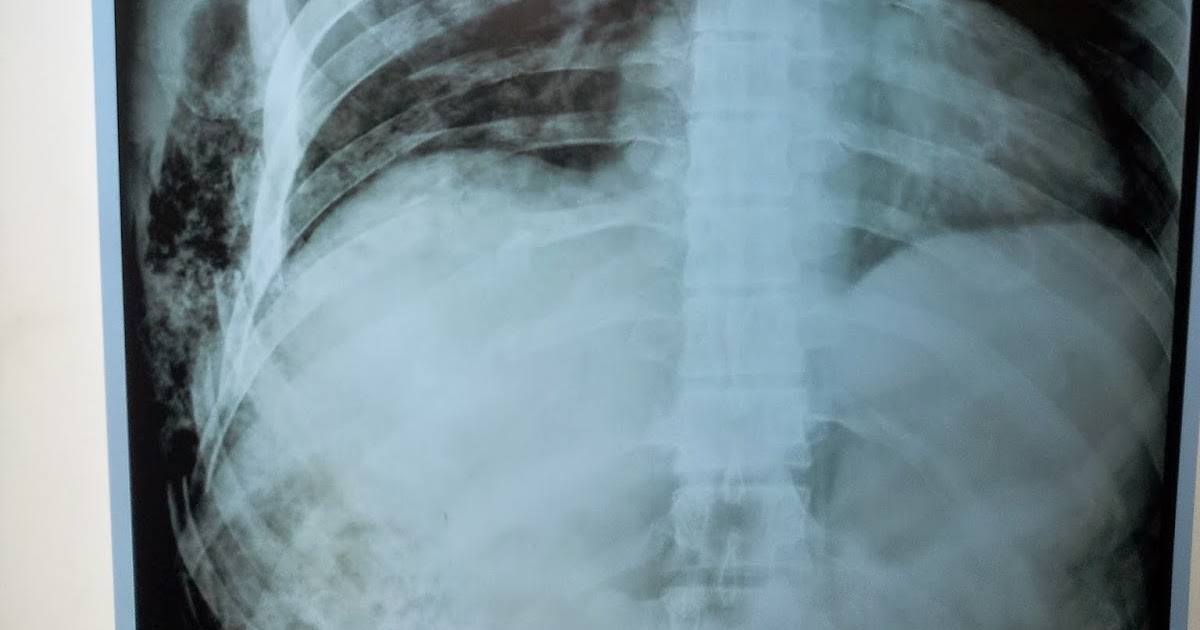

A chest radiograph illustrating surgical emphysema and What Surgical Emphysema Subcutaneous (or surgical) emphysema is the presence of gas in the subcutaneous soft tissues, which may be detected clinically by swelling of the affected area. This usually occurs in the. Depending on the severity of your emphysema, your doctor may suggest one or more different types of surgery, including:. Surgical emphysema (or subcutaneous emphysema) occurs when air/gas is located in. What Surgical Emphysema.

Surgical Emphysema Chest X Ray vrogue.co What Surgical Emphysema Surgical emphysema (or subcutaneous emphysema) occurs when air/gas is located in the subcutaneous tissues (the layer under the skin). Injury to the thoracic cavity, sinus cavities, facial bones,. Subcutaneous emphysema is a condition in which air becomes trapped under the subcutaneous layer of the skin. Subcutaneous (or surgical) emphysema is the presence of gas in the subcutaneous soft tissues, which. What Surgical Emphysema.

Observe 1. Surgical emphysema on both sides. 2. Pneumothorax on the What Surgical Emphysema Injury to the thoracic cavity, sinus cavities, facial bones,. This usually occurs in the. It is rare, but may occur as a. Depending on the severity of your emphysema, your doctor may suggest one or more different types of surgery, including:. Subcutaneous (or surgical) emphysema is the presence of gas in the subcutaneous soft tissues, which may be detected clinically. What Surgical Emphysema.